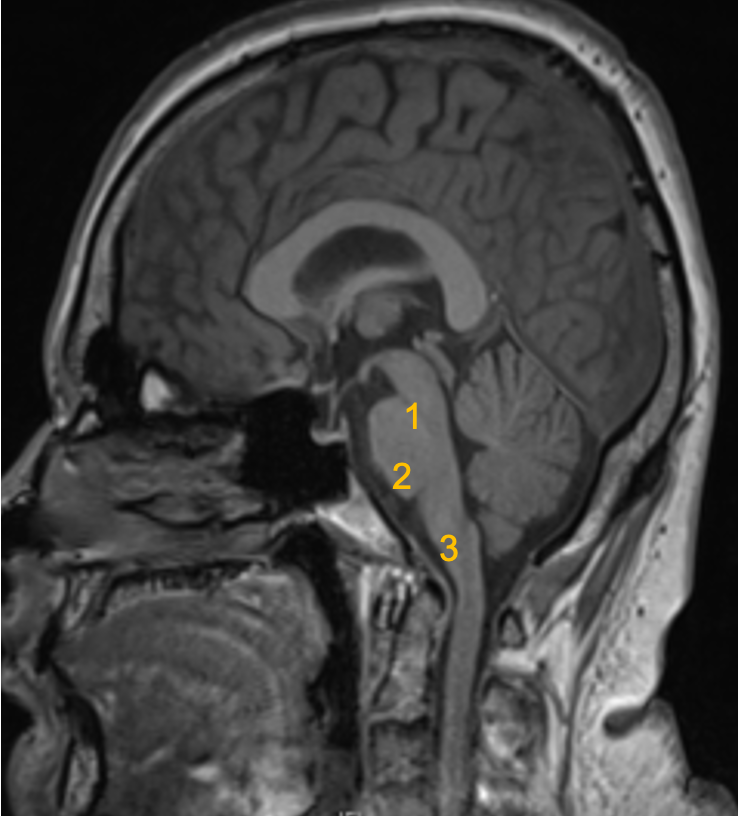

Brain Stem..

Three parts from superior to inferior:

1 Midbrain

2 Pons

3 Medulla oblongata